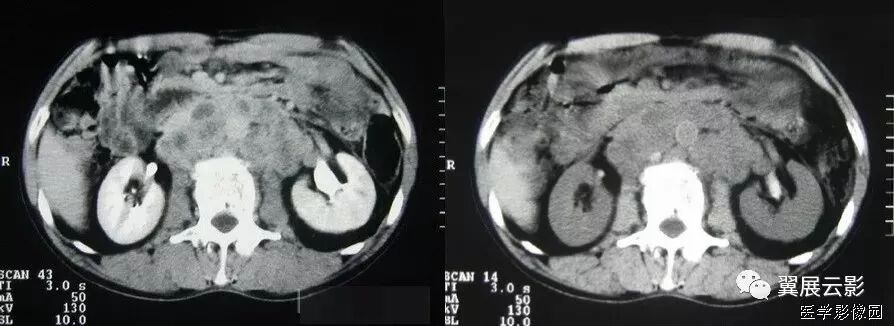

5、肠系膜混浊征

肠系膜脂肪受炎症细胞、液体(水肿、淋巴液和血液)、肿瘤浸润及纤维化的CT表现。当肠系膜被液体或细胞浸润时,其脂肪CT值增加到-40~ -60HU(肠系膜脂肪的CT值类似于皮下及腹膜后脂肪,约-100~-160hu,肠系膜血管常呈横行或断面显示。),动、静脉失去锐利边缘。根据浸润的性质和范围,肠系膜血管可部分或完全模糊,顺着脏层腹膜常能发现肠系膜疾病的线索,在周围脂肪衬托下,肠系膜病变显示更加清晰。

上两幅图:肠系膜上动脉栓塞

下两幅图:十二指肠扭转致肠壁增厚、肠系膜水肿